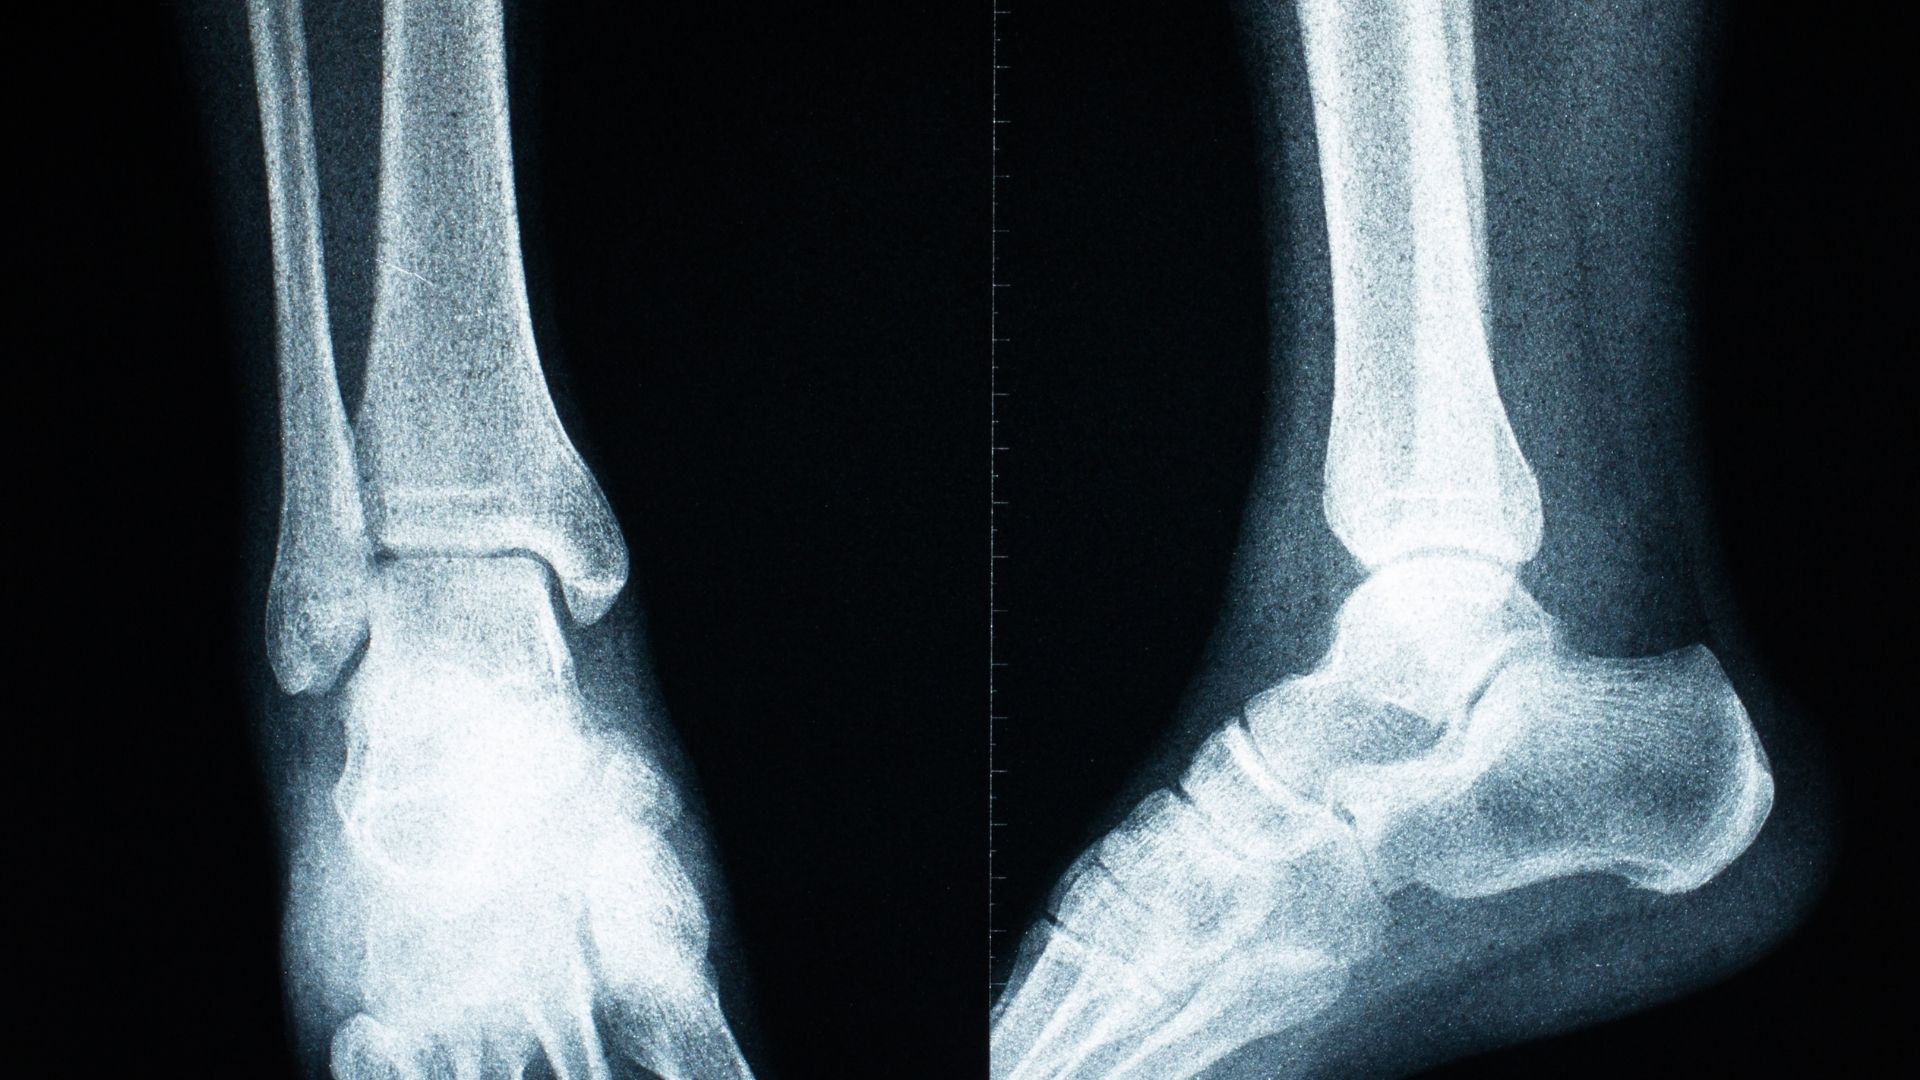

Chụp X-quang chân là kỹ thuật chẩn đoán hình ảnh sử dụng tia X để ghi lại hình ảnh cấu trúc xương và các khớp ở vùng chân. Thông qua hình ảnh thu được, bác sĩ có thể quan sát được tình trạng xương, phát hiện những bất thường như gãy xương, nứt, lệch trục hoặc các dấu hiệu tổn thương khác.

Điểm mạnh của kỹ thuật này nằm ở khả năng cung cấp hình ảnh rõ ràng về cấu trúc xương trong thời gian ngắn. Nhờ đó, bác sĩ có cơ sở để đưa ra chẩn đoán ban đầu và định hướng điều trị phù hợp. Với những trường hợp nghi ngờ tổn thương xương, X-quang thường là bước thăm dò đầu tiên trước khi cân nhắc các phương pháp chẩn đoán chuyên sâu hơn.

Tùy vào vị trí tổn thương và mục đích chẩn đoán, bác sĩ có thể chỉ định chụp X-quang chân ở một hoặc nhiều tư thế khác nhau. Tư thế chụp thẳng giúp đánh giá tổng quan trục xương và cấu trúc khớp. Trong khi đó, tư thế chụp nghiêng hỗ trợ quan sát rõ hơn các khe khớp hoặc những tổn thương khó nhận thấy ở tư thế thẳng.